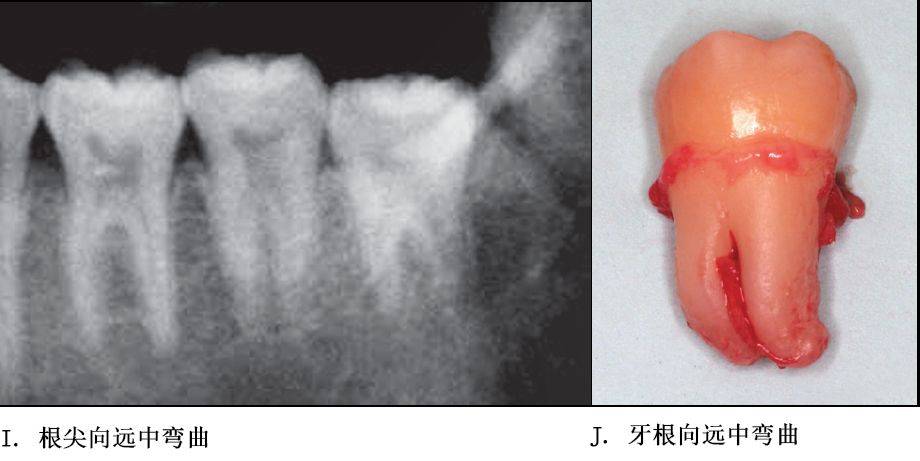

牙根阻力以多根牙、根分歧过大、特长根、U形根、牙颈部倒凹大者阻力较大根尖区以近中弯曲、多向弯曲、根尖肥大者牙根阻力较大。

单根牙、根分叉不大者、合并根、融合根、特短根、锥形根阻力较小。若根尖区向远中弯曲、无弯曲或根尖未形成,则阻力也较小。